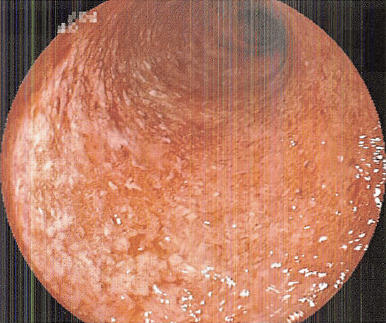

写真のように小指と薬指半分が痺れたり痛みがでます

これは尺骨神経が支配している範囲です